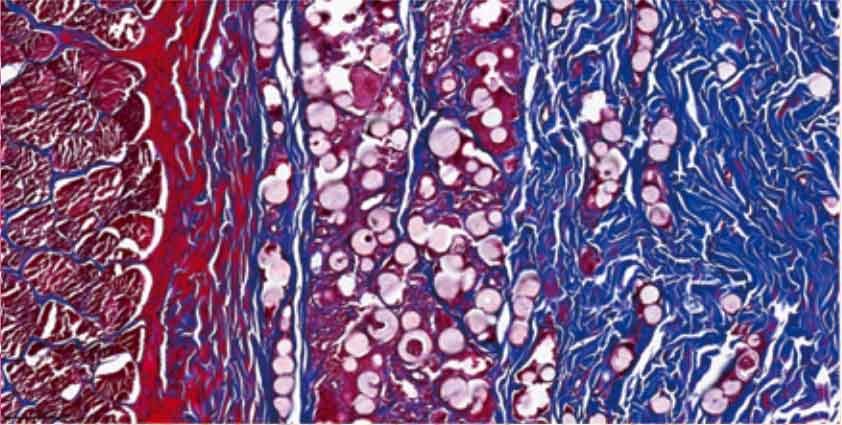

Compared with Control Group, after 6 months of implantation in the body, more fibroblast cells can be seen around the round granular PLLA filler in the deep dermis of the skin for Test Group, indicating the generation of new collagen. Some collagen appears coarse, enveloping the implant. There is less infiltration of inflammatory cells around the implant.